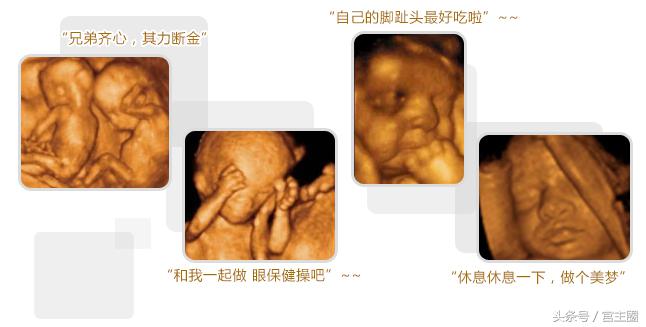

第三次检查:可于孕26周左右进行。此期胎儿皮下脂肪较以上饱满,面部表情也比较丰富,胎儿各个部位较前期更加清晰,不仅是对以上各类畸形的诊断更加明确,而且胎儿面部的各种表情,如吃手指、打呵欠、哭闹、喝羊水等表情清晰可见。